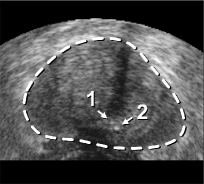

The framework was validated on 278 registrations of 295 US volumes from 17 patients. The 17 reference images were acquired shortly before the intervention, and the tracking images were acquired after a biopsy shot. The clinical protocol was approved by the ethical committee of the XXX hospital, Town, Country, and all patients consented to participate to the study. The images were acquired with a GE Voluson and a RIC5-9 endorectal US probe. The algorithms were executed on a 4-core 2.6Ghz processor. In order to provide a reference gold standard for the evaluation of registration accuracy, experts manually segmented 467 point fiducials that were clearly identifiable on multiple images (e.g. calcifications and cysts). The distances between fiducial pairs were measured after registration to estimate the local accuracy. Note that the unavoidable segmentation error increases the measured error in average; this approach hence underestimates accuracy. Accuracy was computed for all registrations that were qualified as valid by experts after visual inspection, which represent 97,8 of the registrations. The results for both rigid and elastic registration are given in Tab. 1, and a visual illustration of the registration performance is given in Fig. 2. Fig. 3 shows 3D biopsy maps created with our biopsy tracking system.